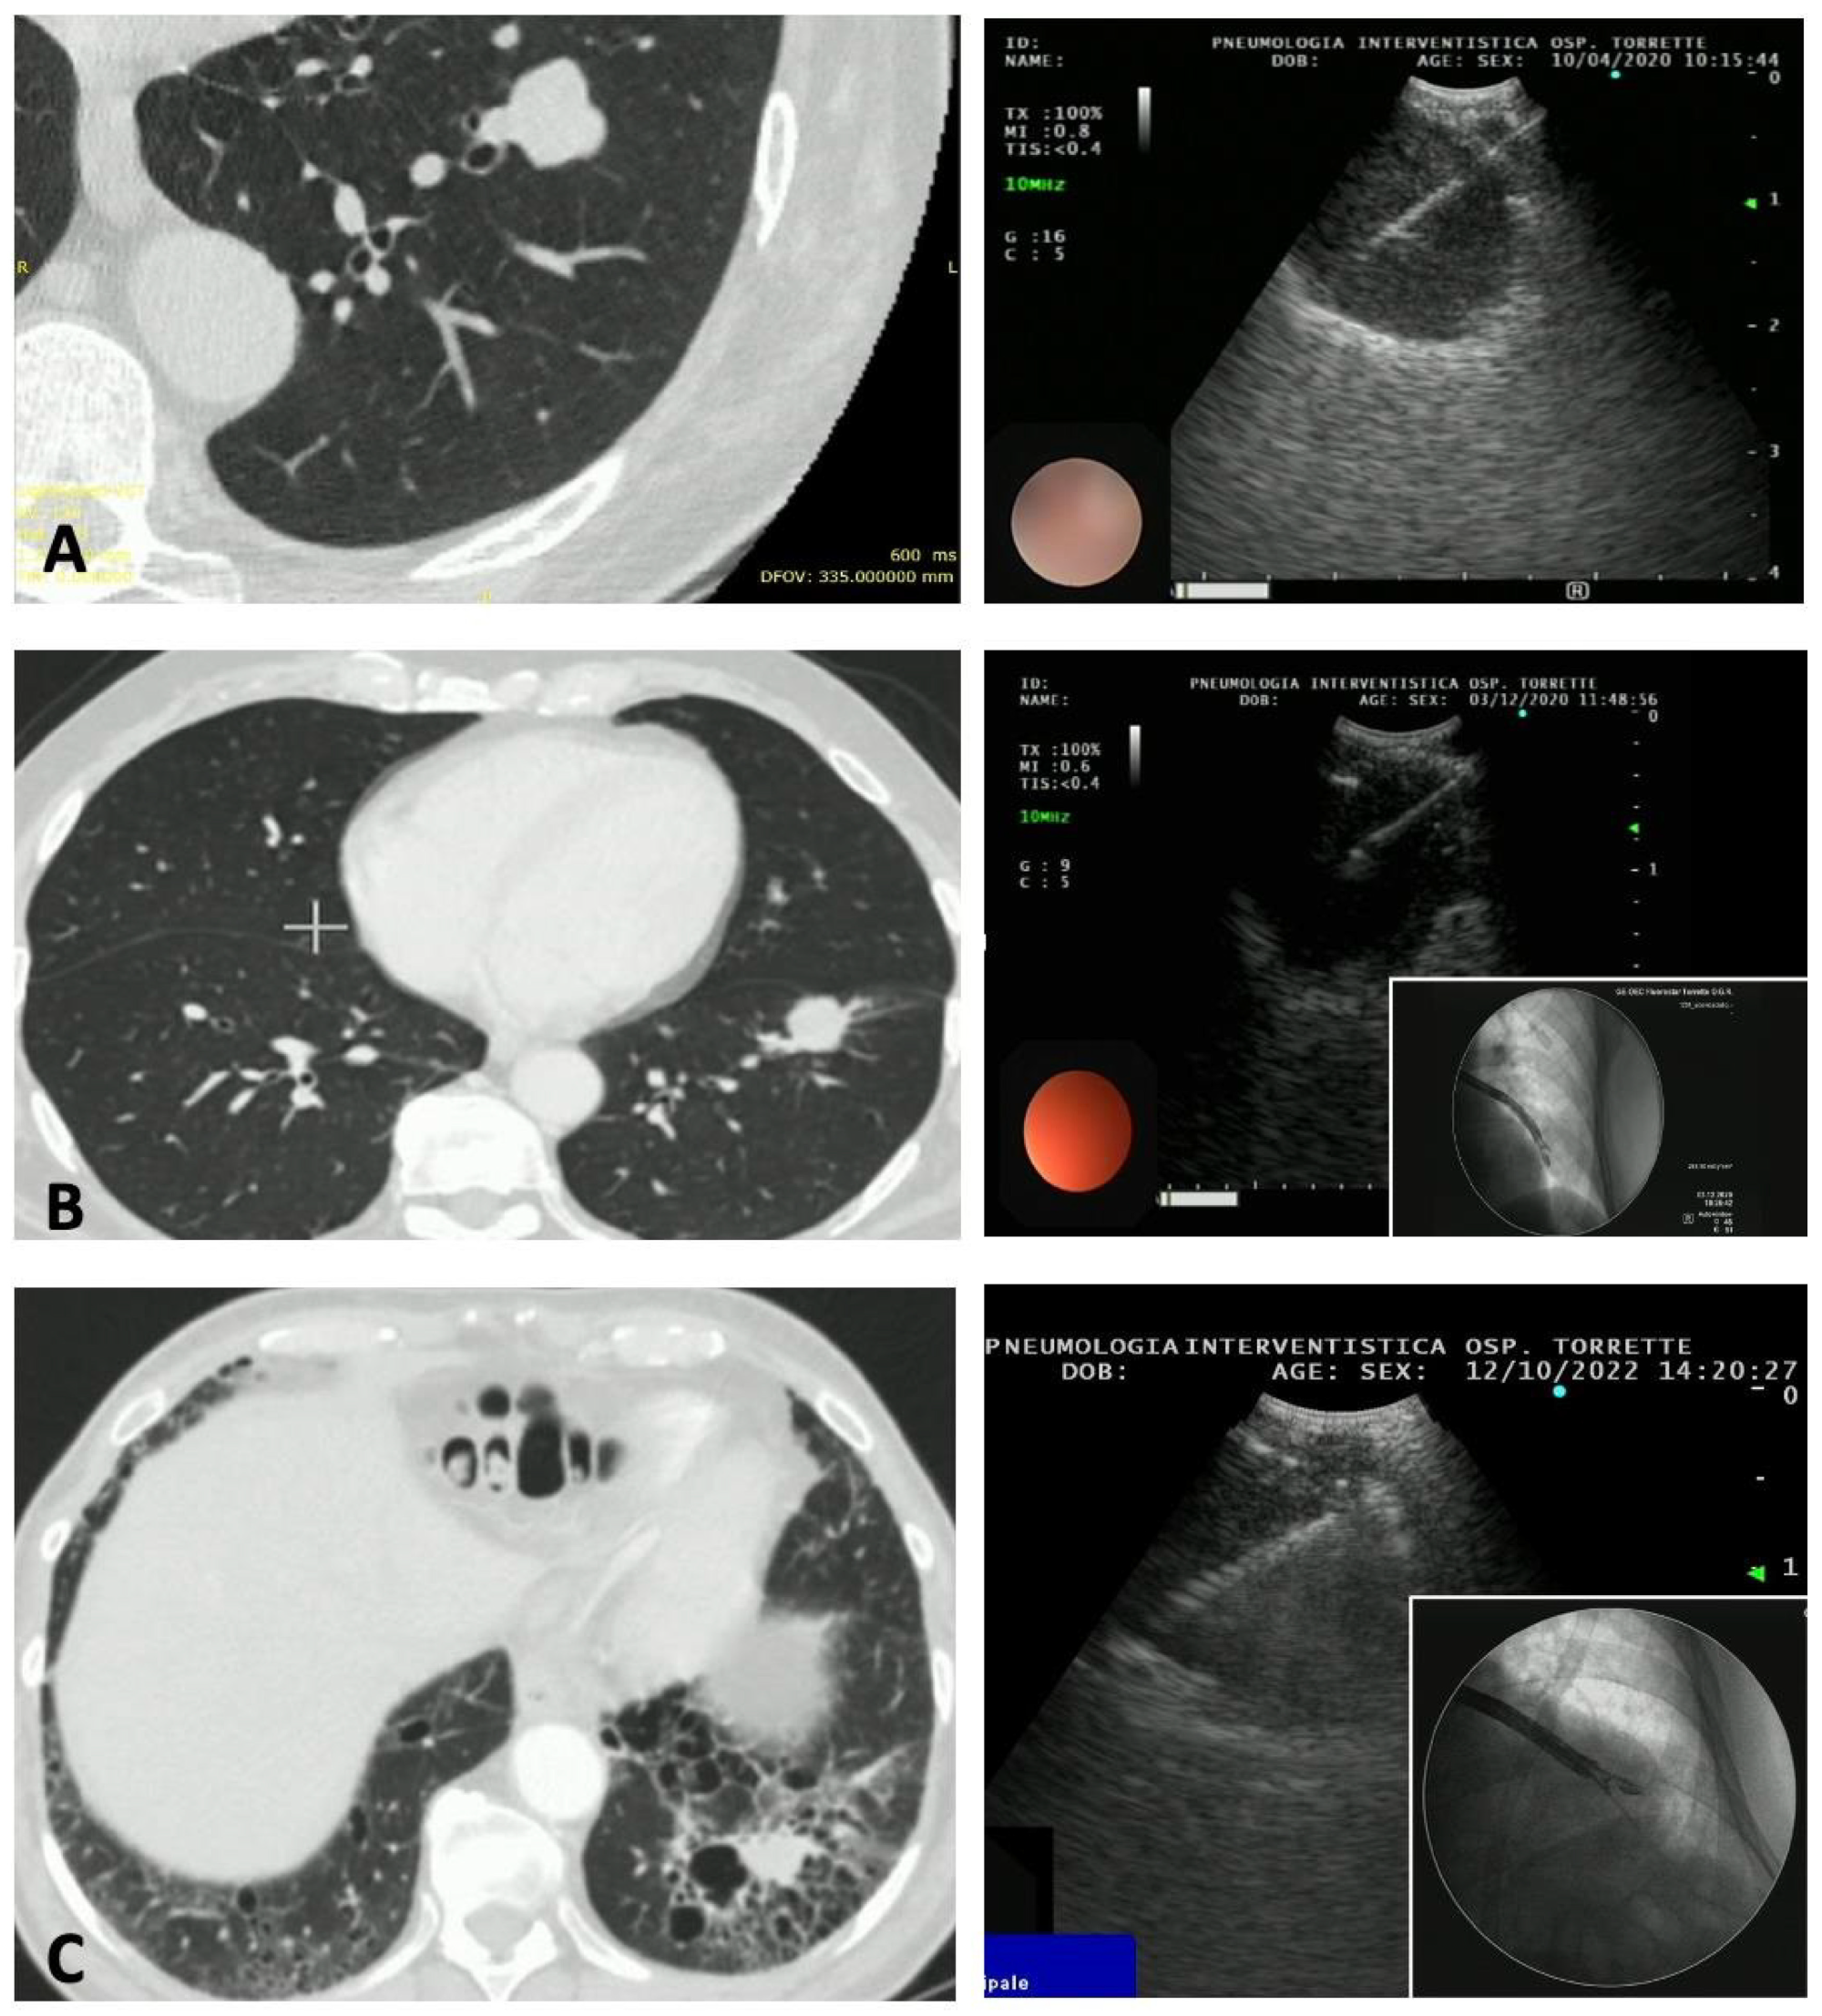

2. Materials and Methods

2.2. Procedure